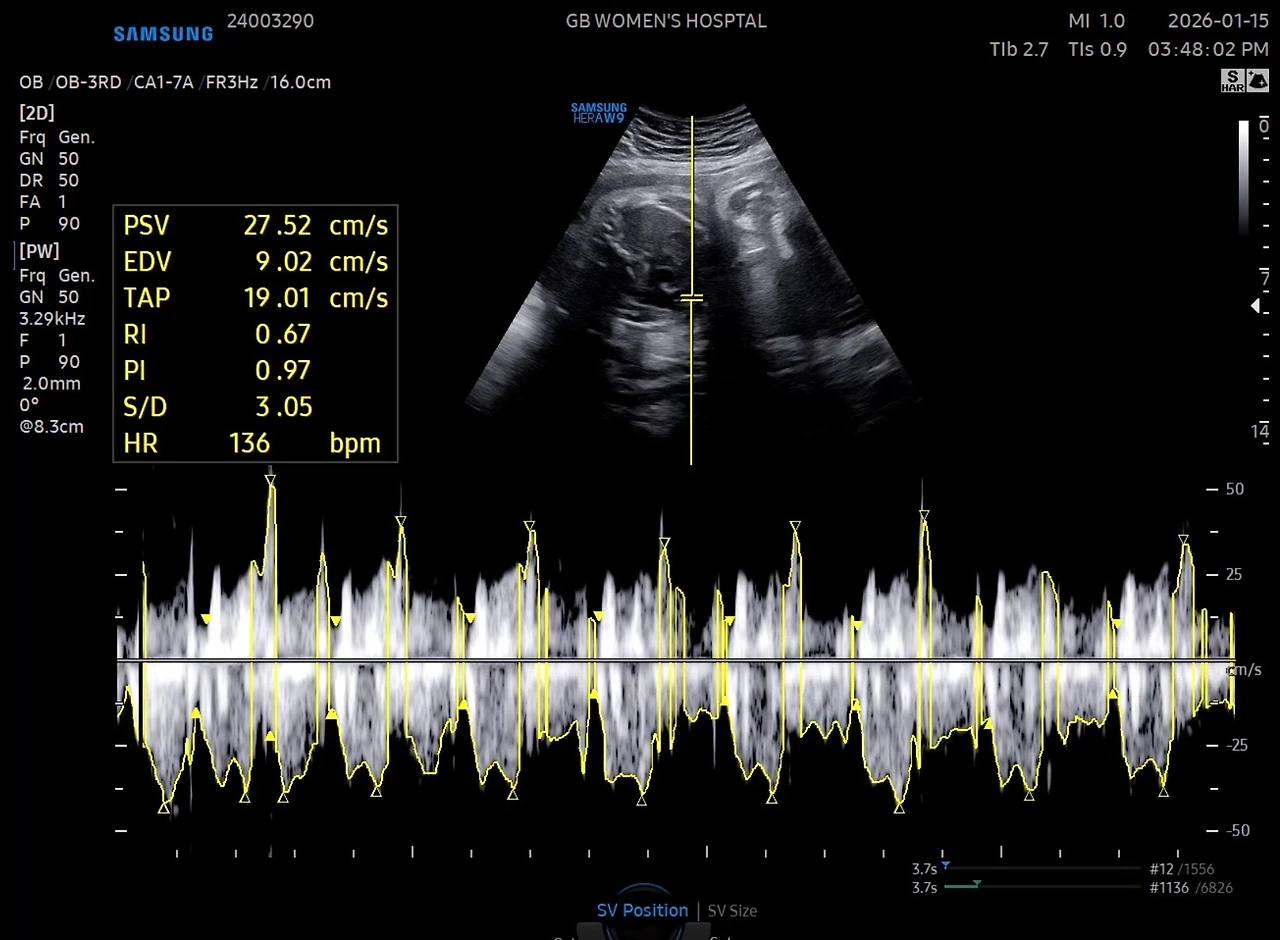

어제는 출산 전 마지막 산부인과를 갔다

그런데 웬걸 의사 선생님께서 가슴아래에 초음파

기기를 대었을 때 “여기 대퇴골이고요” 하는 데?

“여기가 머리네요”

하고 배 아래쪽을 말씀하셨다

“오.. 그럼 아기가 돈 거예요?”

라고 하니,

“아니 돈 건 아니고 고개를 돌린 정도예요”

라고 하셔서

“지난주까지는 역아였는데, 지금 역아예요?”

라고 물어보니

“아! 역아는 아니고 지금 아래쪽에 머리가 있어요”

하셨다